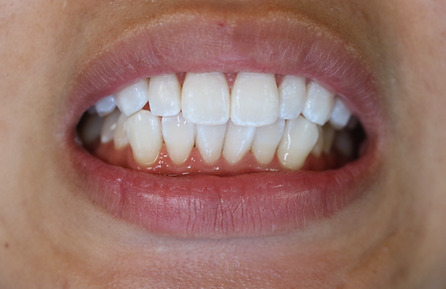

2ホワイトニング【治療例1】

治療前

治療後